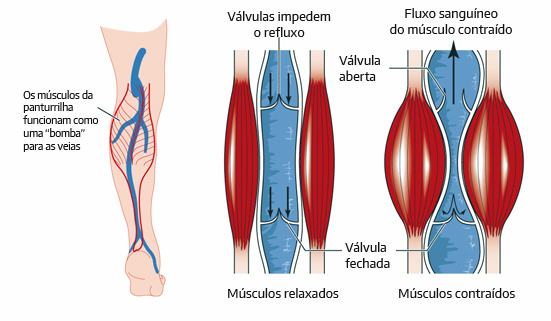

Pode parecer surpreendente, mas os seres humanos têm, de fato, uma espécie de “segundo coração” localizado nas pernas. Conhecido como músculo sóleo, essa estrutura vital, localizada na panturrilha, desempenha um papel crucial para a saúde do corpo, agindo como uma bomba natural que ajuda a impulsionar o sangue de volta ao peito.

Esse mecanismo, chamado de “bomba da panturrilha”, funciona de forma plena apenas com o movimento. Seja ao caminhar, ao correr ou até mesmo ao mexer os pés enquanto estamos sentados, a contração muscular das panturrilhas é o que garante que o sangue desoxigenado retorne ao coração de maneira eficiente.

Quando o corpo permanece inativo por longos períodos — como em viagens de avião, ônibus ou durante jornadas de trabalho prolongadas —, o fluxo sanguíneo pode diminuir, fazendo com que o sangue se acumule nas pernas. Essa estagnação aumenta consideravelmente o risco de trombose venosa profunda, um quadro grave em que coágulos de sangue se formam nas veias, e outros distúrbios circulatórios.